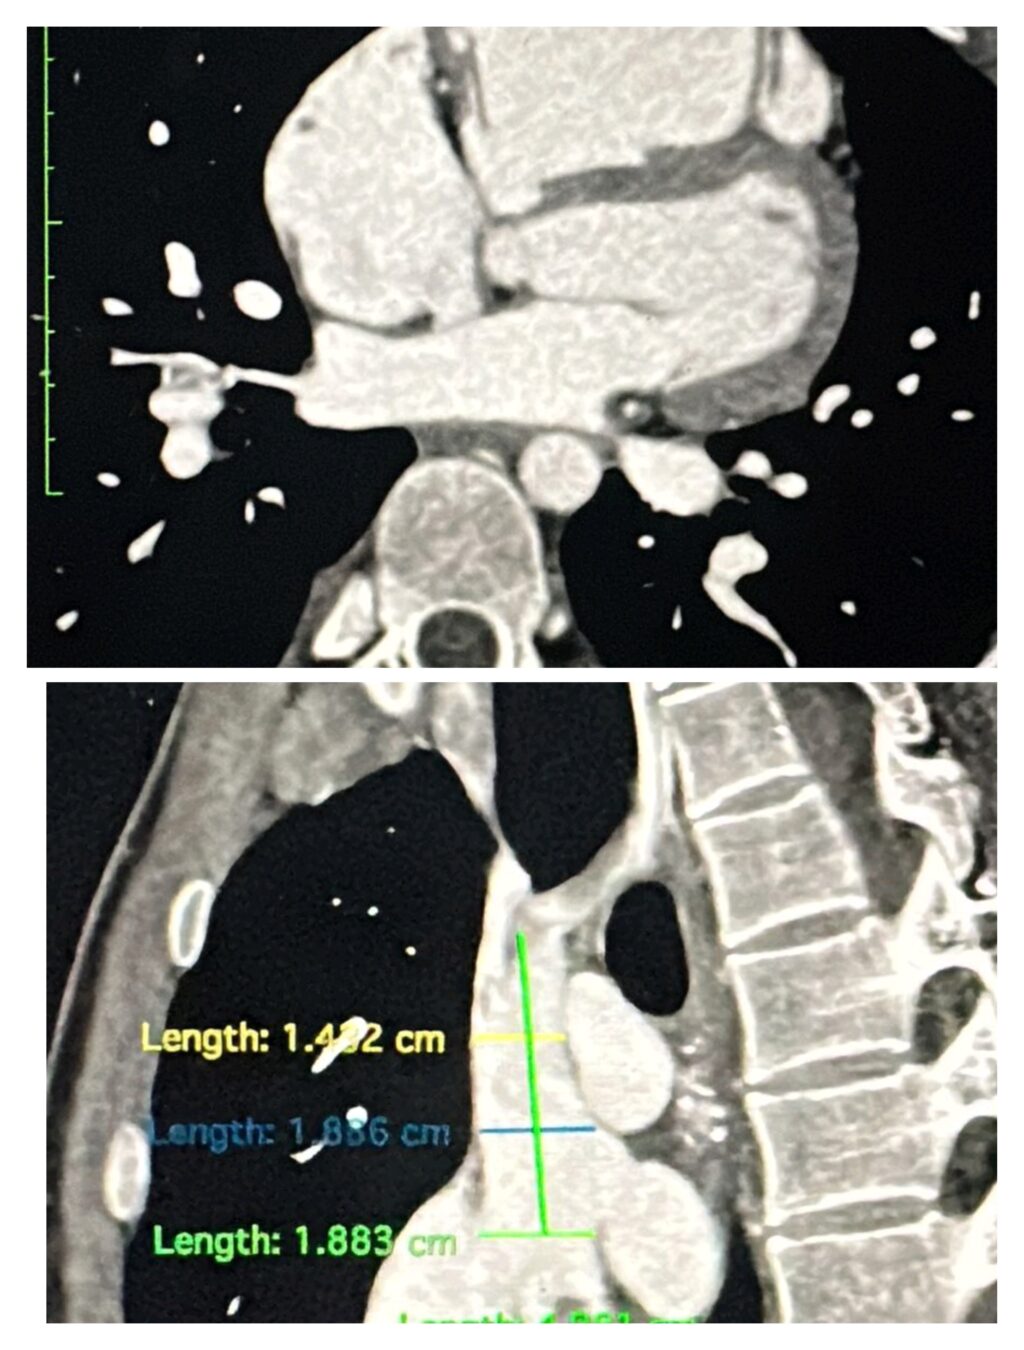

एम्स भोपाल ने पहली बार साइनस वेनोसस एट्रियल सेप्टल डिफेक्ट (ASD) का क्लोजर एक हाइब्रिड कवर स्टेंट की मदद से सफलतापूर्वक किया। यह उपलब्धि हृदय रोग उपचार के क्षेत्र में एक अहम कदम है। यह उन्नत प्रक्रिया विश्व-भर में तेजी से स्वीकार की जा रही है, हालांकि उत्तर भारत के केवल कुछ ही केंद्र इस तकनीक का उपयोग कर रहे हैं। इस जटिल मामले में रोगी की संरचना चुनौतीपूर्ण थी। इसमें एक अतिरिक्त दाहिनी ऊपरी पल्मोनरी वेन (RUPV) मौजूद थी, जिसे प्रक्रिया के दौरान बंद होने से बचाना आवश्यक था। इसके अलावा, सीवीसी-आरए (SVC–RA) जंक्शन काफी चौड़ा था, जिसके लिए स्टेंट का विशेष तरीके से फैलाव करना जरूरी था ताकि रक्त प्रवाह सुचारु बना रहे। टीम ने एक विशेष हाइब्रिड कवर स्टेंट का उपयोग किया, जिसके एक सिरे पर 15 मिमी का अनकवर्ड भाग होता है। अतिरिक्त नस की सुरक्षा के लिए, 5F JR कैथेटर को कवर और अनकवर भाग के जंक्शन पर स्टेंट स्ट्रट्स के बीच से सावधानीपूर्वक निकाला गया। इसके बाद, 28 मिमी BMV बैलून का उपयोग करके स्टेंट को सही तरीके से फिट किया गया और किसी भी शेष शंट को समाप्त कर दिया गया।

यह तकनीक, जिसमें RA–SVC जंक्शन पर बैलून से फ्लेयरिंग की जाती है, अब तक वर्णित नहीं की गई थी। परिणाम पूरी तरह सफल रहा। RUPV का पूरा रक्त प्रवाह बिना किसी रुकावट के बाएँ आलिंद (Left Atrium) में पहुंचाया गया। यह उपलब्धि एम्स भोपाल के लिए एक नया मील का पत्थर है और यह दर्शाती है कि संस्थान दुर्लभ और जटिल हृदय उपचारों में भी उत्कृष्टता की ओर अग्रसर है।